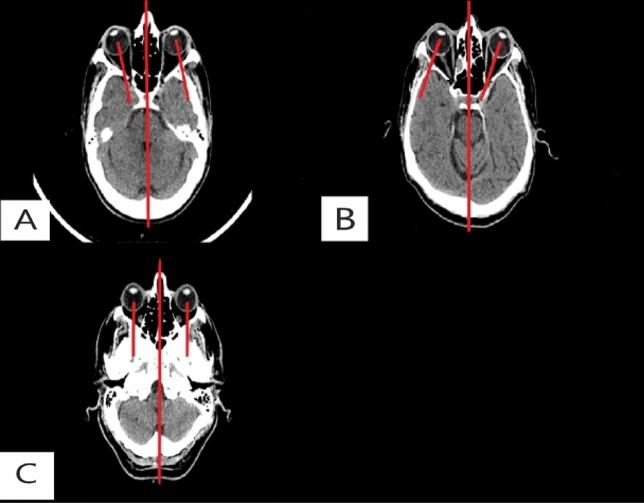

Scans were classified as showing rightward globe, leftward globe, or undeviated indeterminate globe. Indeterminate scans were those where the axes were not visible. If there was movement of the ocular axes across the midline between slices, the scans were classified as undeviated (Fig. 2).

Fig. 2.

Non contrast head CT showing: A right vestibular neuronitis–nystagmus slow phase to the right VES Sign-rightward deviation. B Left vestibular neuronitis–nystagmus slow phase to the left VES Sign-leftward deviation. C A patient from group B (Non-VN etiology) with undeviated “intermedita” globe